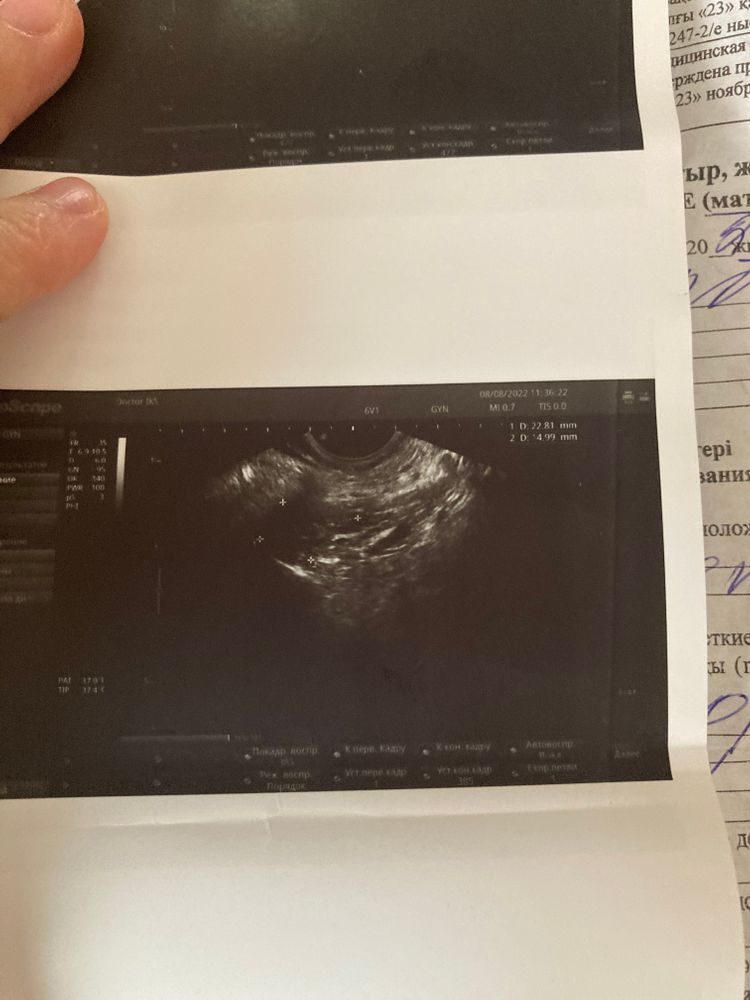

ФолликулометрияДевочки кто понимает узи снимки есть тут Желтое тело?

Последний снимок сказала жидкость за маткой